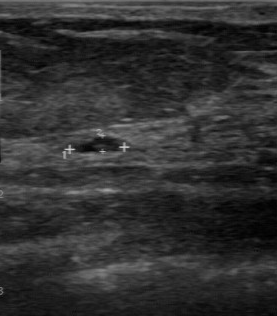

US imaging presents a substantial domain gap compared to other medical imaging modalities; building an US-specific foundation model therefore requires a specialized large-scale dataset. To build such a dataset, we crawl a multitude of platforms for human medical US with instance annotations and open-access availability: Papers with Code, Google Dataset Search, GitHub, Google Scholar, Kaggle, ResearchGate, Mendeley dataset, Zenodo and Data in Brief. Through this process, we arrive at US-43d (see Fig.1.a), a collection of 43 datasets covering 20 different clinical applications, containing 282,321 annotated segmentation masks from both 2D and 3D scans. US-43d captures organs and lesion of various shapes, sizes, and textures across clinical applications such as cardiac, fetal head, thyroid, and breast lesions, as illustrated in Fig.2, providing a comprehensive view of the medical ultrasound landscape. Table 1 provides detailed information on the US-43d dataset, including dataset names, access links, and the number of images and segmentation masks available in each.

For testing, we select three diverse datasets from US-43d: BUS-BRA [BUSBRA] (breast lesions, 1875 images), MMOTU2D [mmotu] (ovarian lesions, 1469 images), and GIST514-DB [GIST514] (gastrointestinal stromal tumors, 514 images). GIST514-DB is included as an outlier in our selection, as it is the only dataset in US-43d with radial acquisition. We evaluate on the official test split of each dataset. Together they include linear and radial probes, endoscopic and non-endoscopic US, and span multiple clinical applications, anatomical regions, lesion types, and imaging techniques, enabling exhaustive evaluation of UltraSam’s generalizability. We reserve 5% of each training dataset for validation and use the remaining 95% for training. We preprocess images by removing label-background overlaps (common in 3D US), cropping backgrounds occupying more than 50% of image pixels, and using sagittal views for 3D images.